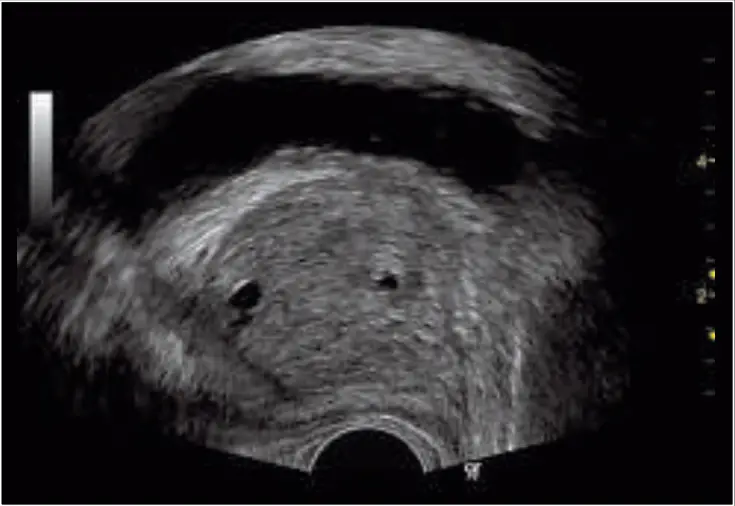

| Sagittal prostate showing cystic structure imaging with the E8CS probes using fundamental imaging and SRI | Apical four-chamber view of the adult heart with color Doppler using the 3S probe |

Speckle Reduction Imaging (SRI). Heighten your visibility of organs and lesions with high-definition contrast resolution that suppresses speckle artifacts while maintaining true tissue architecture.

CrossXBeam™. Enhance tissue and border differentiation with real-time spatial compounding acquisition and processing.

Harmonics. Increase resolution and cystic clarity with a combination of coded harmonics and Phase Inversion Harmonics.